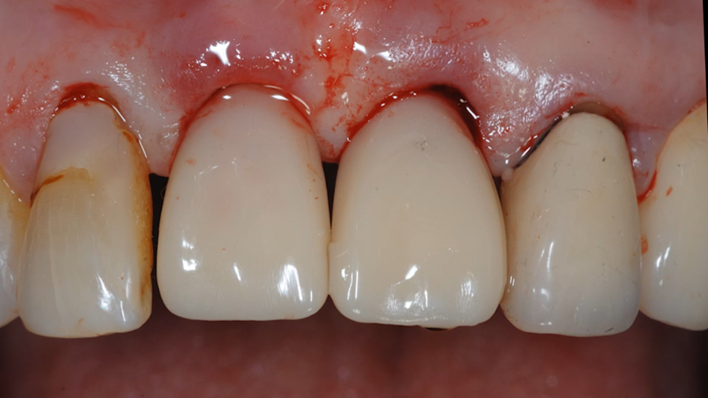

Clinical case: : R2GATE guided surgery & immediate implant placement

- Courtesy of Dr. Kwang Bum Park, Korea -

Dr. Kwang Bum Park, immediate loading, digital guided surgery, digital ONE-DAY implant, maxillary anterior, #21, guided surgery, immediate loading, AnyRidge, R2GATE, Mega ISQ, MEG Torq, R2GATE Full Surgical Kit

implant system, R2GATE Guide, R2GATE full surgical kit, Mega ISQ